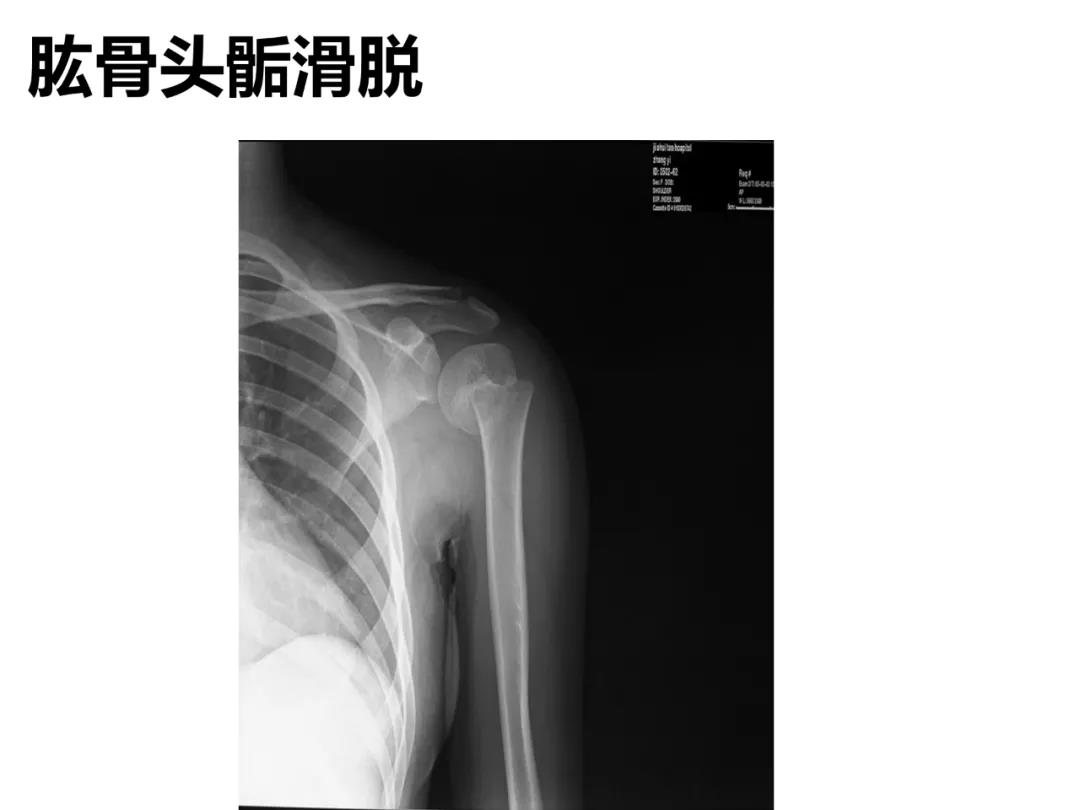

小儿骨科X线片汇总,临床读片宝典!